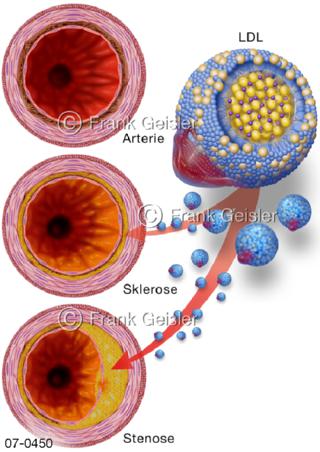

Bildergalerie Herz, Blutkreislauf

Bilder zu Herz, ein muskuläres Hohlorgan, das den menschlichen Körper durch rhythmische Kontraktionen mit Blut versorgt und dadurch die Durchblutung der Organe sichert, das Kreislaufsystem zeigt den Transport von arteriellem sowie venösem Blut durch das kardiovaskuläre System (Herz-Kreislauf-System), bestehend aus Blutgefäßen, Lymphgefäßen und dem Herz